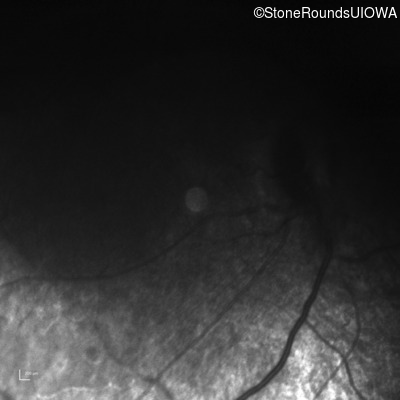

Infrared Fundus Photograph - Right - No Light Perception

Exemplar